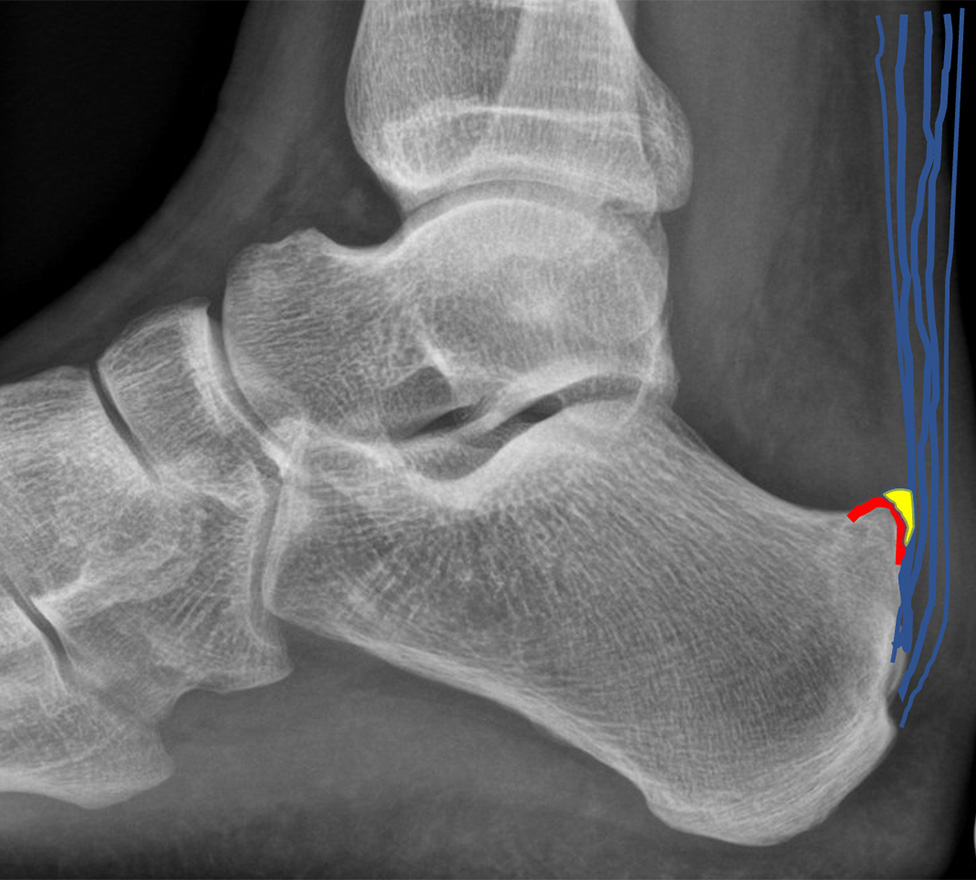

Die Achillessehne ist täglich starken Belastungen ausgesetzt. Unterschieden wird zwischen der häufigeren Form der Achillessehnenentzündung in der Mitte der Sehne und einer Entzündung am Sehnenansatz (Enthese) am Fersenbein. Letztere kann zu einer Verknöcherung des Achillessehnenansatzes und damit zu einem oberen (dorsalen) Fersensporn führen *. Eine Sonderform stellt die Entzündung der Achillessehne mit einer Reizung des Schleimbeutels durch einen herausstehenden Teil des Fersenbeins (Haglund-Deformität) dar, der bei Bewegung des Fusses nach oben gegen die Achillessehne drückt und diese reizt.

Die Haglund-Deformität ist ein vergrösserter Knochen am Fersenbein nahe des Achillessehnenansatzes, der zu einer Reizung und Entzündung des Schleimbeutels zwischen der Achillessehne und des Knochens führen kann. Dabei kann auch die Achillessehne geschädigt werden *.

Diagnose

Ein Fersensporn zeigt sich als kleine, spitze Verhärtung am Ansatz der Achillessehne. Auf einem Röntgenbild sind die knöchernen Veränderungen gut zu erkennen. Zur Beurteilung der Vernarbung und Entzündung ist womöglich eine Magnetresonanztomographie (MRT bzw. engl. MRI für magnetic resonance imaging) oder eine Ultraschalluntersuchung erforderlich.